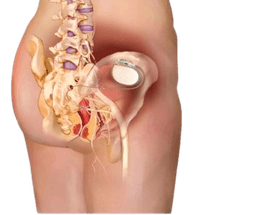

Sacral Nerve Stimulation-SNS

Sacral nerve stimulation (SNS) is a procedure that helps the patient with problems of bowel and bladder. Moreover, sacral neuromodulation therapy helps to improve and restore normal bladder or bowel function. Specifically, sacral nerve stimulation (SNS) in India uses an implanted device that sends mild electric impulses to stimulate nerves that control the function of bowel and bladder. These nerves, in turn, help to manage the function of peep and poop. Consequently, the method changes the signals between the brain, spinal cord, bowel and bladder. This function, therefore, is known as sacral neuromodulation therapy. -br Urinary and fecal incontinence has a severe impact on the life of a person. Sometimes it can be the reason for discomfort, embarrassment or it can increase the dependency on others. Patients who have no result with conventional therapies, SNS plays an important role for such treatments.